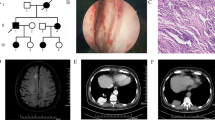

The proband of the HHT family was born in 1967 and is from Shanxi province of China. The patient was admitted for hemoptysis, and a chest radiograph did not find any abnormality in his lungs. His laboratory tests, such as platelet counts and coagulation function, were normal. To determine the bleeding site causing hemoptysis, we performed bronchoscopy on this patient. Results showed hemorrhagic telangiectasia in the tracheal and bronchial mucosa (Fig. 1). The patient told us that he had seizures, and there was a higher incidence rate of epistaxis and seizure in his family members than in other residents, especially when the family members were infants or teenagers. Some family members were admitted to the hospital for seizure and were diagnosed with epilepsy. Therefore, we obtained clinical data from the whole family (32 living members), and the pedigree is shown in Fig. 2 (the proband is III-11). Blood samples from 23 family members were collected, 9 of which exhibited epistaxis and 7 were diagnosed with epilepsy when they were infants. Their platelet-related laboratory tests of platelets were normal, with mean platelet counts of 266.30 × 109 ± 65.57 × 109/L (normal range: 150–350 × 109/L) and platelet activity of 71.80 ± 11.85% (normal range: 50–150%).

Phenotypes and NAPG genotypes of the HHT pedigree. Squares are used for males, circles for females, and slashes for the deceased. III-11 is the proband (arrow). Black symbols show members with both epistaxis and epilepsy. Shadow symbols show members with epistaxis only. Whole-exome sequencing was conducted on individuals labeled with a star (upper right star). A/A or A/G indicates the genotype of NAPG c.784A > G